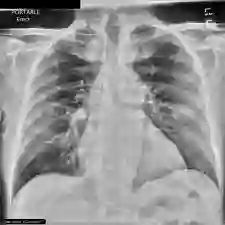

Recent advances in image-text pretraining have significantly enhanced visual understanding by aligning visual and textual representations. Contrastive Language-Image Pretraining (CLIP) has played a pivotal role in multimodal learning. However, its focus on single-label, single-granularity alignment limits its effectiveness in complex domains such as medical imaging, where images often correspond to multiple high-level labels (e.g., disease categories) across different annotation granularities (e.g., diagnostic description, clinical explanation). To address this, we propose Multi-Granular Language Learning (MGLL), a contrastive learning framework designed to improve both multi-label and cross-granularity alignment. MGLL leverages structured multi-label supervision, integrates textual descriptions across granularities, and introduces soft-label supervision with point-wise constraints to enhance alignment. MGLL employs smooth Kullback-Leibler (KL) divergence to ensure cross-granularity consistency while maintaining computational efficiency as a plug-and-play module for vision-language models. Pretrained on our constructed large-scale multi-granular datasets and evaluated across multiple datasets, MGLL outperforms other state-of-the-art methods in downstream tasks. The code is available at https://github.com/HUANGLIZI/MGLL.